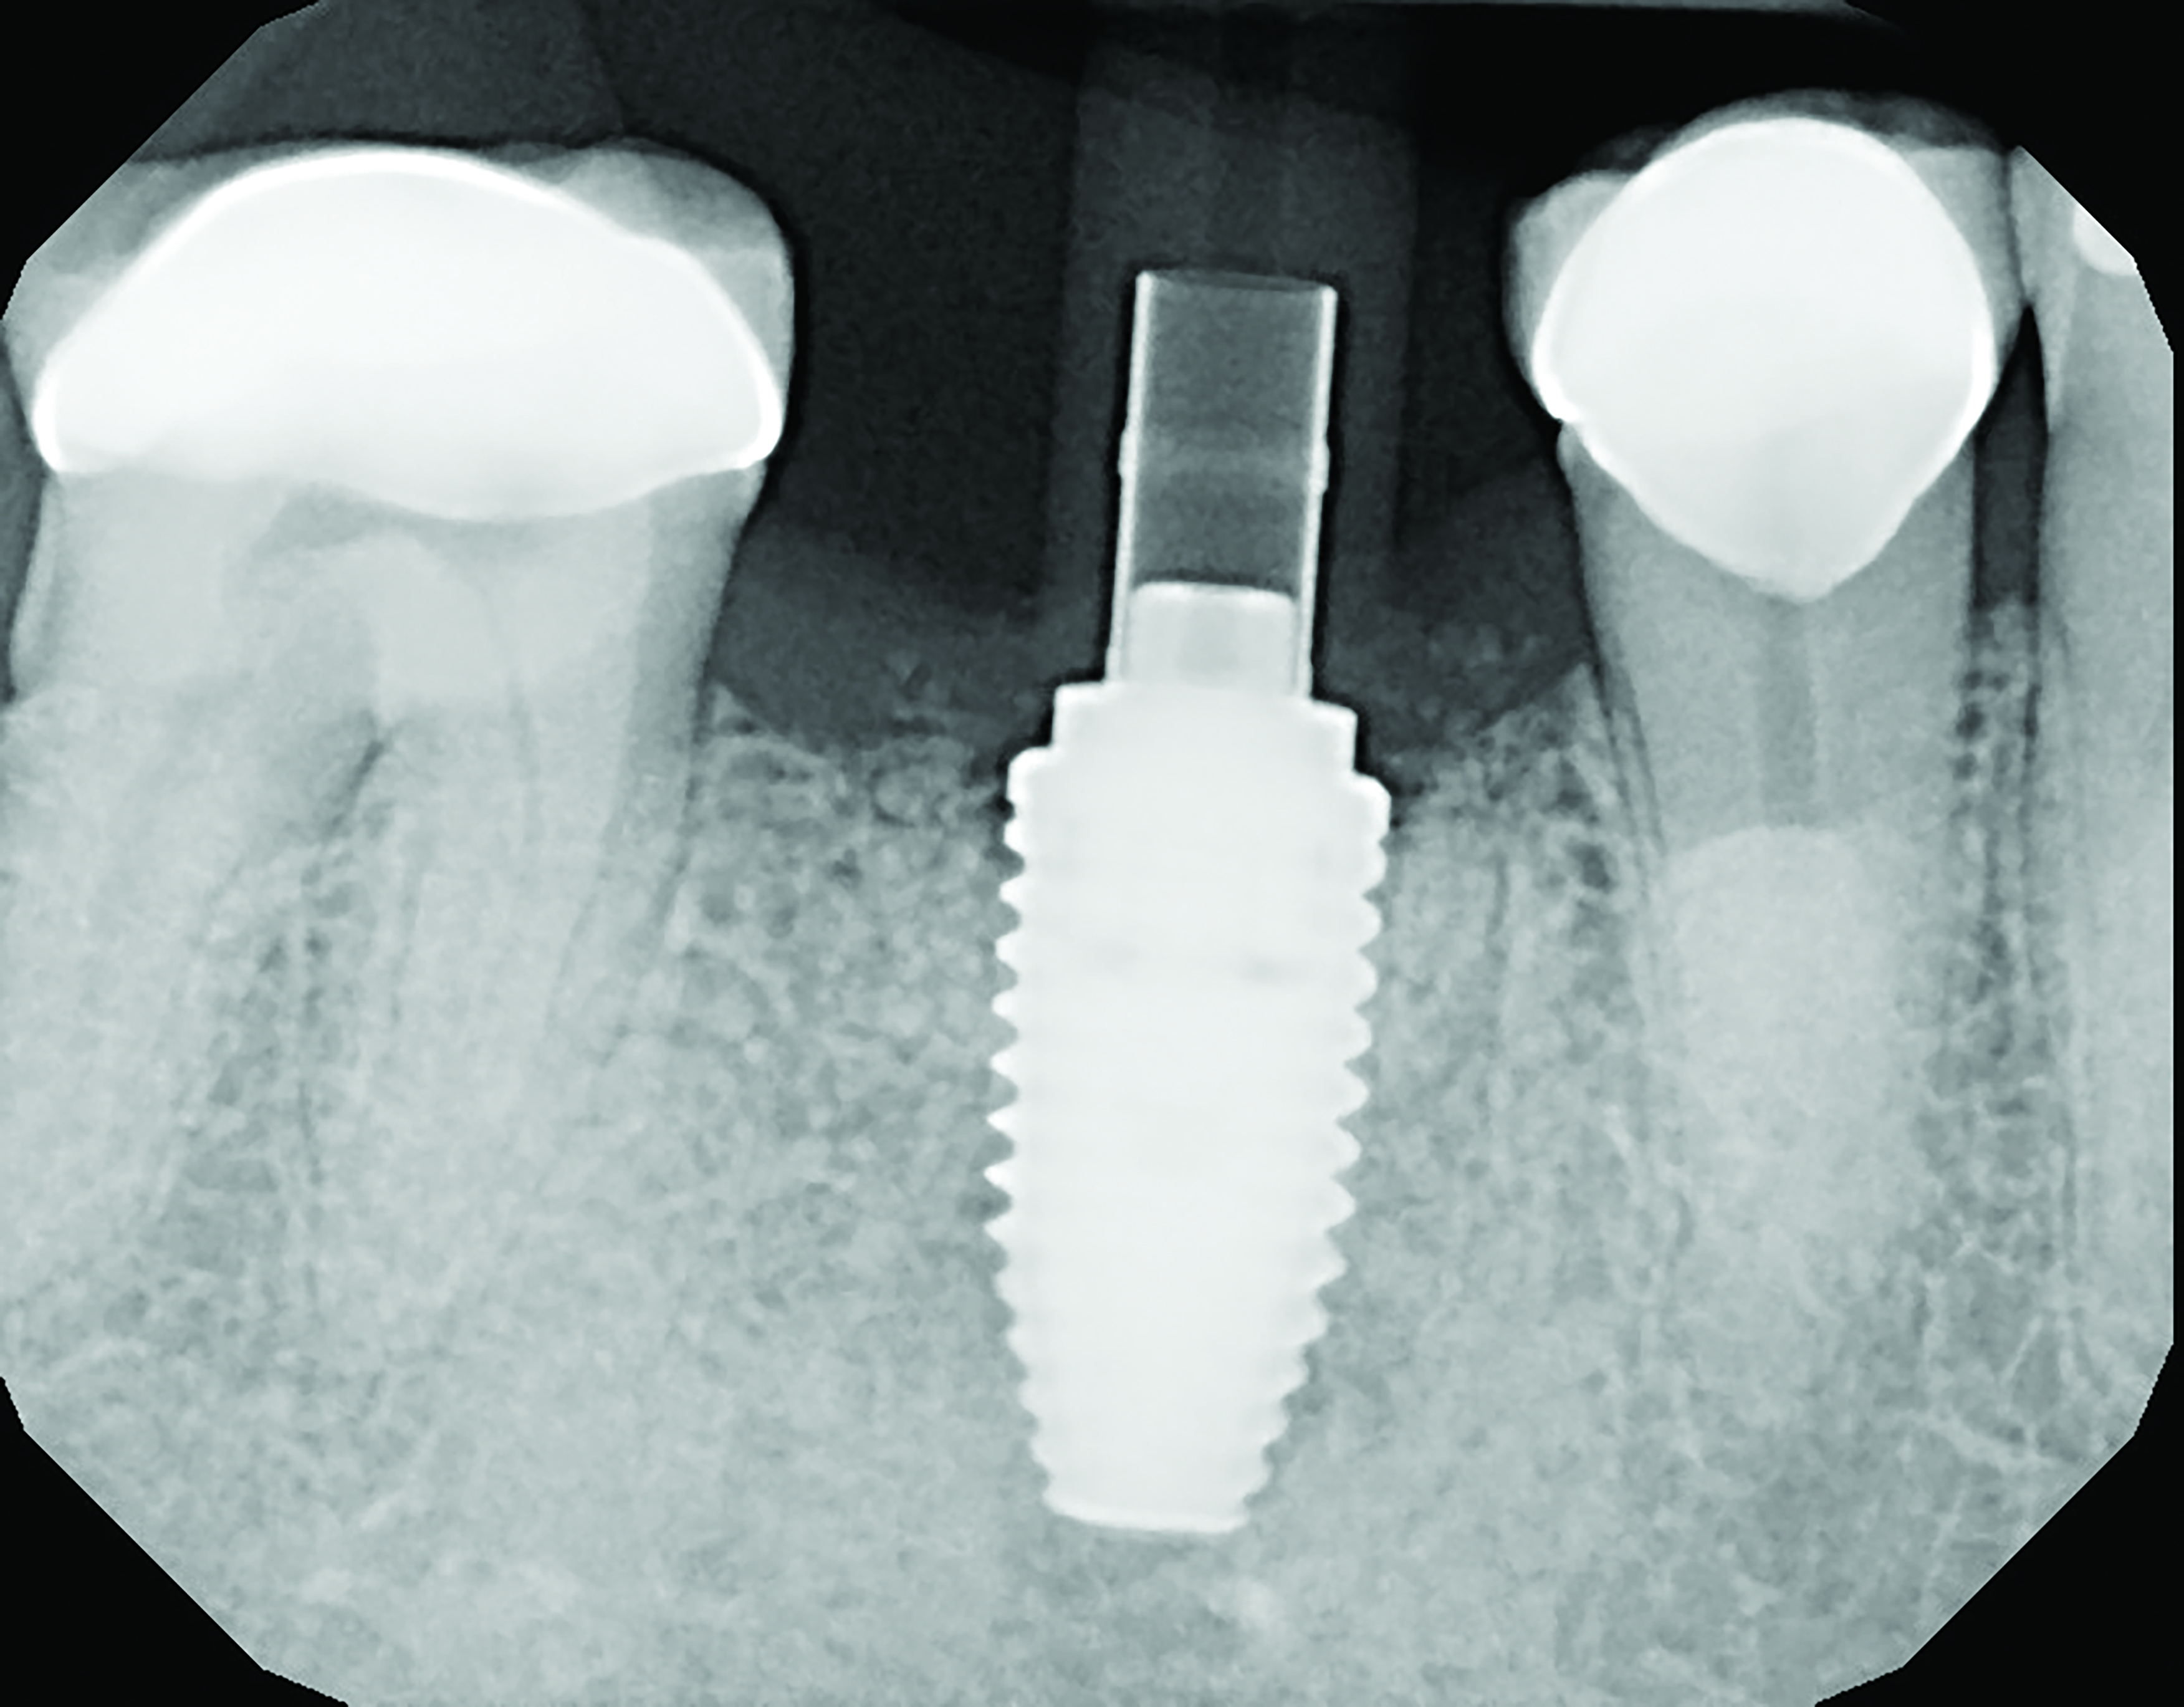

A mandibular right first molar was extracted due to an advanced Class III furcation and an irreversible pulpitis—a combination lesion. An immediate implant placement protocol was elected, and a PEEK abutment was placed on the implant (Figure 1). After 3 months of healing, a scan body was placed on the osseointegrated implant (Figure 2 and Figure 3), and an intraoral scan was taken (TRIOS Pod) (Figure 4) for the fabrication of a screw-retained crown.

Fig 1. Immediate implant placement with a PEEK healing abutment to contour soft tissue, mandibular right first molar.

Figure 1

Fig 3. Confirmation of seating of scan body.

Figure 3